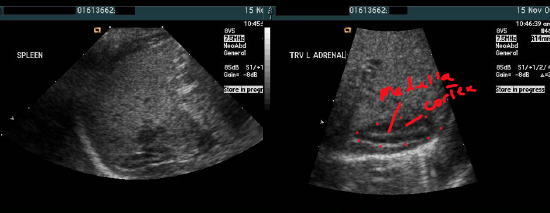

describe the cortex and medulla echogenicity

Cortex: thick, hypoechoic

–

Medulla: thin, hyperechoic

*can’t differentiate b/t medulla and cortex after childhood.